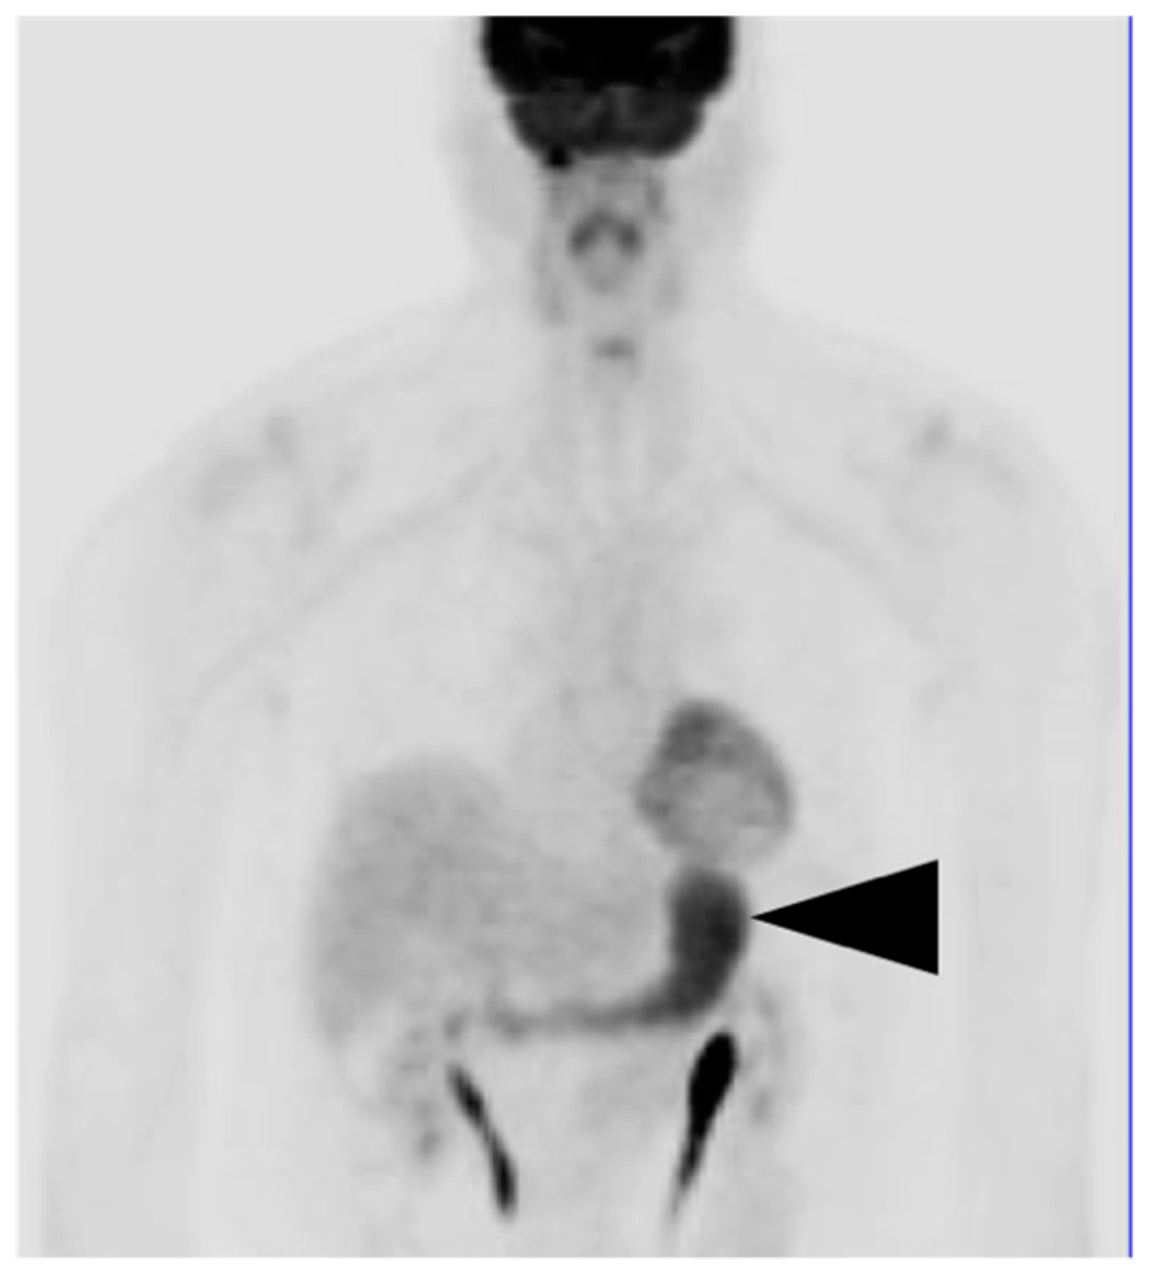

7. Adrenal Cancer